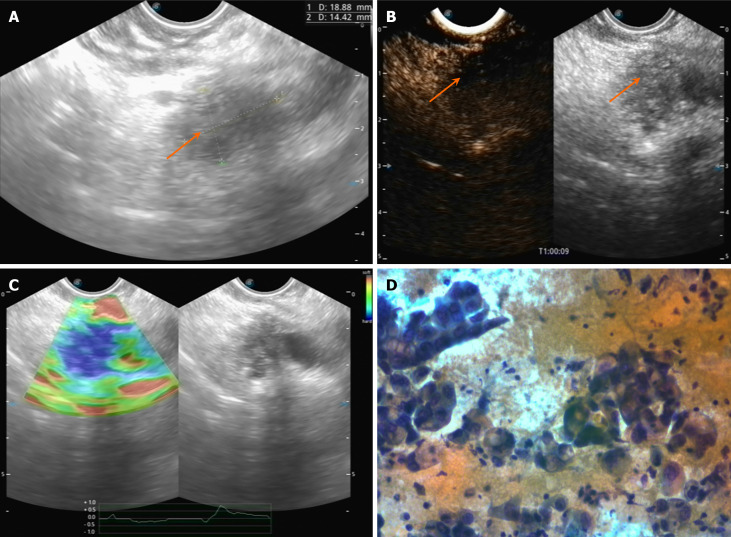

胰腺癌被认为是癌症死亡的主要原因之一,是胃肠道癌症相关死亡的第二大常见来源。手术切除是目前唯一确定的治疗方法;然而,症状的细微出现往往导致晚期诊断,只有10%-15%的患者有资格进行手术干预。实现潜在根治性切除的主要障碍是远处转移性疾病的存在或邻近主要血管结构的侵犯。本文综述了超声内镜在胰腺肿瘤诊断和分期中的重要作用。我们以“胰腺癌”和“内窥镜超声”为关键词,系统地检索了PubMed、MEDLINE和Web of Science。对相关研究进行了回顾和分析。超声内镜(EUS)对胰腺癌的诊断和分期是有效的,既往研究报道EUS对t分期的准确率为63% ~ 94%,对n分期的准确率为44% ~ 82%,但仍有局限性,需要与其他诊断方法综合应用以评估远处转移的手术可切除性。我们的综述旨在揭示胰腺癌分期的价值。

Pancreatic cancer is recognized as one of the leading causes of cancer mortality, representing the second most common source of cancer-related deaths within the gastrointestinal domain. Surgical resection is currently the only definitive treatment; however, the subtle emergence of symptoms often leads to a diagnosis at an advanced stage, with merely 10%-15% of patients being eligible for surgical intervention. The primary obstacle to achieving a potential radical resection is the presence of distant metastatic disease or invasion of adjacent major vascular structures. This review aims to highlight the critical role of endoscopic ultrasound in the diagnosis and staging of pancreatic tumors. We systematically searched PubMed, MEDLINE and Web of Science by using 'pancreatic cancer' and 'endoscopic ultrasonography' as keywords. Relevant studies were reviewed and analyzed. Endoscopic ultrasonography (EUS) is efficient in the diagnosis and staging of pancreatic cancer, past studies reported the accuracy of EUS is 63% to 94% for T-staging and 44% to 82% for N-staging but there are still limitations that need to be comprehensively applied with other diagnostic methods to evaluation of distant metastasis for surgical resectability. Our review aims to reveal the value for the staging of pancreatic cancer.